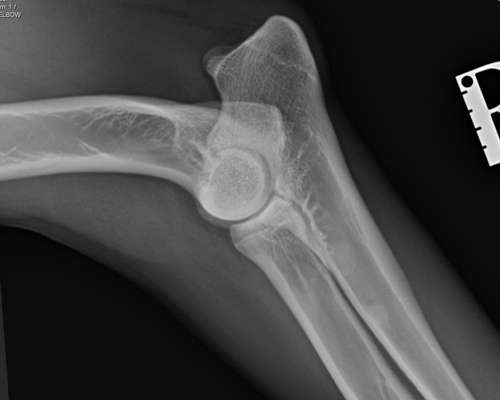

Elle Rechts

Hab Röntgen Bilder für euch. Lagerung nicht perfekt und bin gespannt was der Doktor zum LÜW sagt...

Lendenübergangswirbel

Sieht irgendwie "schief" aus.🤔

Was sagt der Tierarzt zu der hüfte da sind die Pfannen nicht weit genug ausgebildet das ist jetzt nicht so tragisch wäre aber sehr wahrscheinlich hd nochzugelassen wenn überhaupt

Ja 16/17und 17 sehen auffällig aus kann aber auch von der schlechten lagerung sein